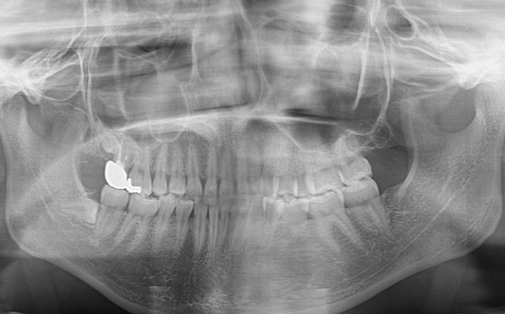

Before

After

左上の親知らずの歯を移植しました。20代前半の症例です。

ご自身の歯のため親和性が高く、移植後も不自由なく機能しています。